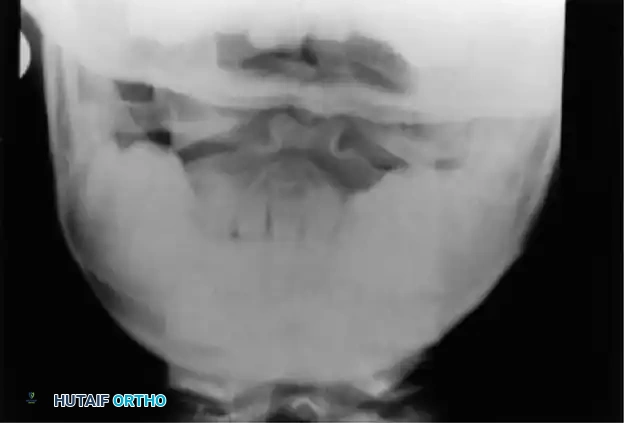

Image

Fig. 37-4 Lateral radiograph (A) and open-mouth odontoid radiograph (B) showing os odontoideum.

• Aplasia: Appears as a slight depression between the superior articulating facets on the open-mouth view.

• Os Odontoideum: A distinct space is visible between the C2 body and the free ossicle. The ossicle is typically half the size of a normal dens, with smooth, sclerotic borders. This must be differentiated from an acute Type II odontoid fracture, which presents with a thin, irregular, non-sclerotic radiolucent line.